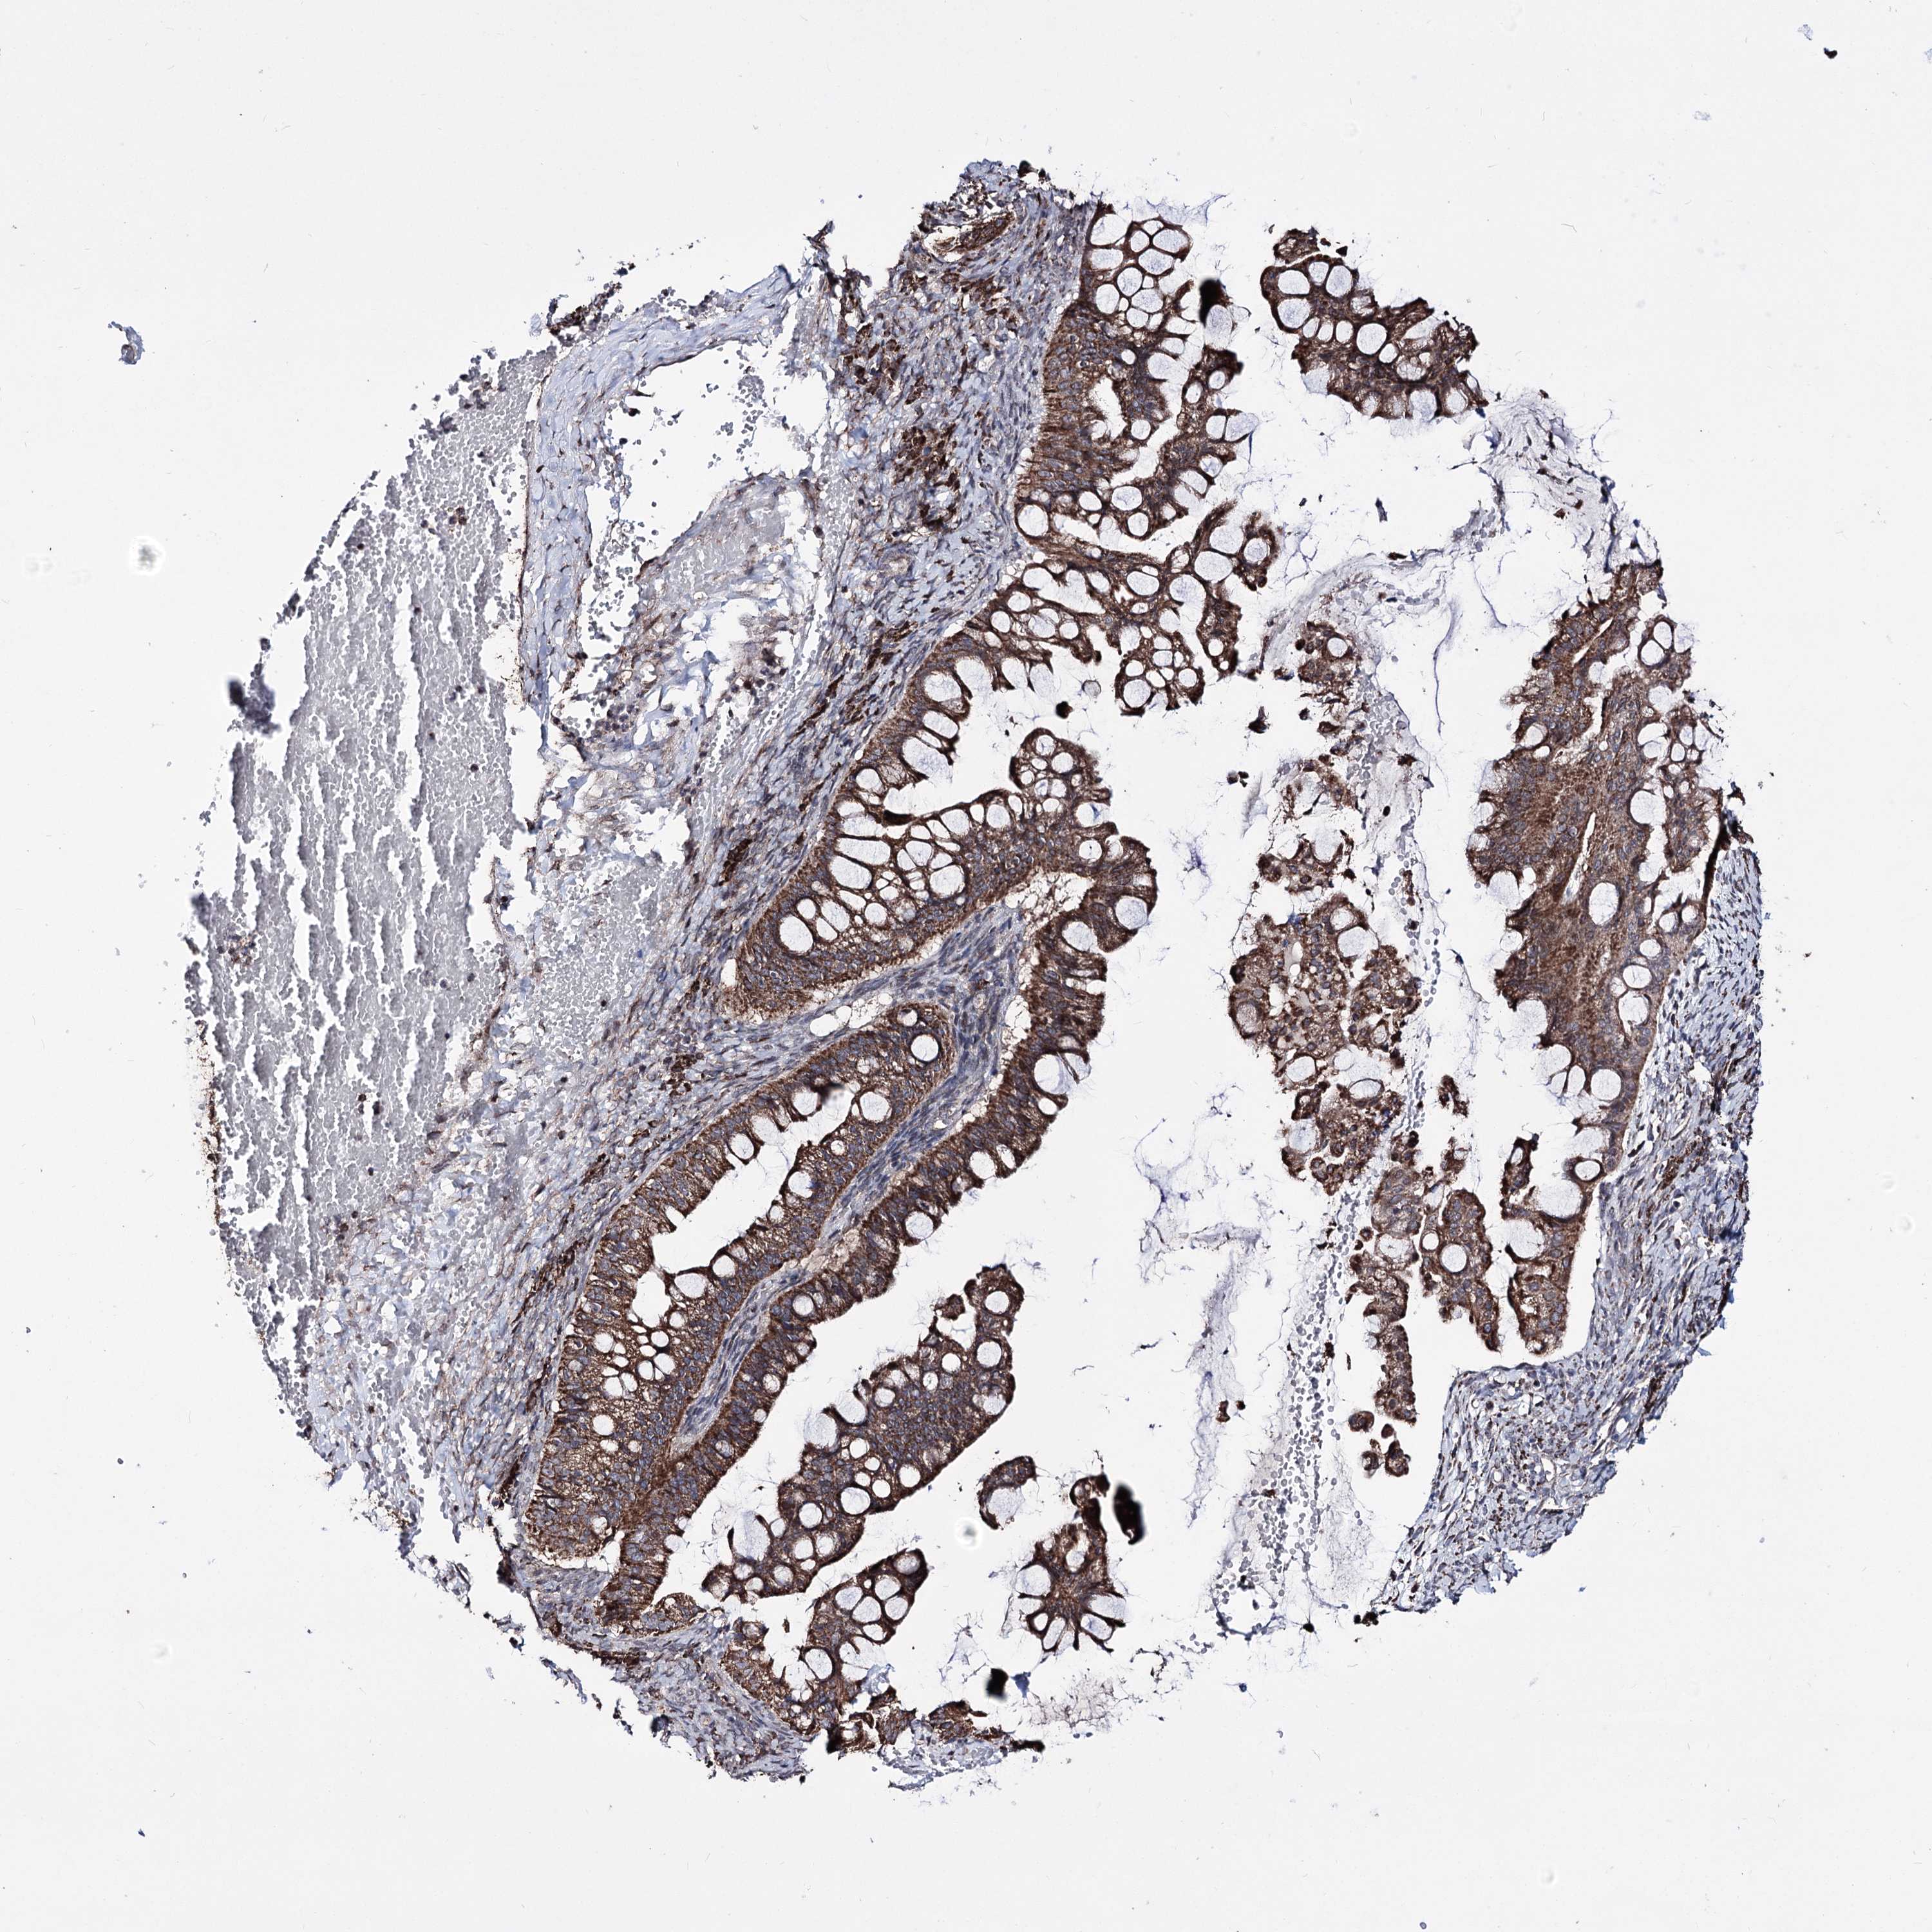

OVARIAN CANCER - Protein expressioni

A mouse-over function shows sample information and annotation data. Click on an image to view it in a full screen mode. Samples can be filtered based on level of antibody staining by selecting one or several of the following categories: high, medium, low and not detected. The assay and annotation is described here.

Note that samples used for immunohistochemistry by the Human Protein Atlas do not correspond to samples in the TCGA dataset.

Antibody stainingi

Antibody staining in the annotated cell types in the current human tissue is reported as not detected, low, medium, or high, based on conventional immunohistochemistry profiling in selected tissues. This score is based on the combination of the staining intensity and fraction of stained cells.

Each image is clickable and will lead to virtual microscopy that enables deeper exploration of all samples and also displays staining intensity scores, fraction scores and subcellular localization as well as patient and tissue information for each sample.

Antibody HPA038122

Staining

High

Medium

Low

Not detected

Intensity

Strong

Moderate

Weak

Negative

Quantity

>75%

75%-25%

<25%

None

Location

Nuclear

Cytoplasmic/membranous

Cytoplasmic/membranous,nuclear

Cystadenocarcinoma, serous, NOS

Carcinoma, endometroid

Cystadenocarcinoma, mucinous, NOS

Carcinoma, NOS